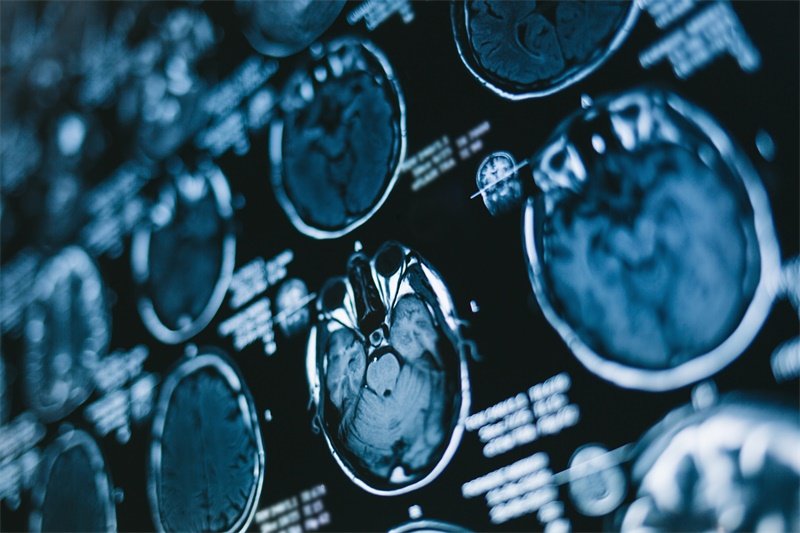

右侧大脑镰旁占位的诊断通常依赖于影像学检查。磁共振成像(MRI)是最常用的诊断工具,能够清晰地展示脑部结构及病变特征。

此外,计算机断层扫描(CT)也可以作为辅助检查来评估占位的大小和性质。对于怀疑存在肿瘤的患者,生物活检可能是进一步确认病变性质的重要手段。

确认右侧大脑镰旁占位的性质通常需要进行影像学检查,如MRI或CT扫描。这些检查能够清楚显示病变的大小、形状和位置,从而帮助医生判断其性质。此外,如果影像学结果不明确,生物活检可以提供关键的组织学信息。